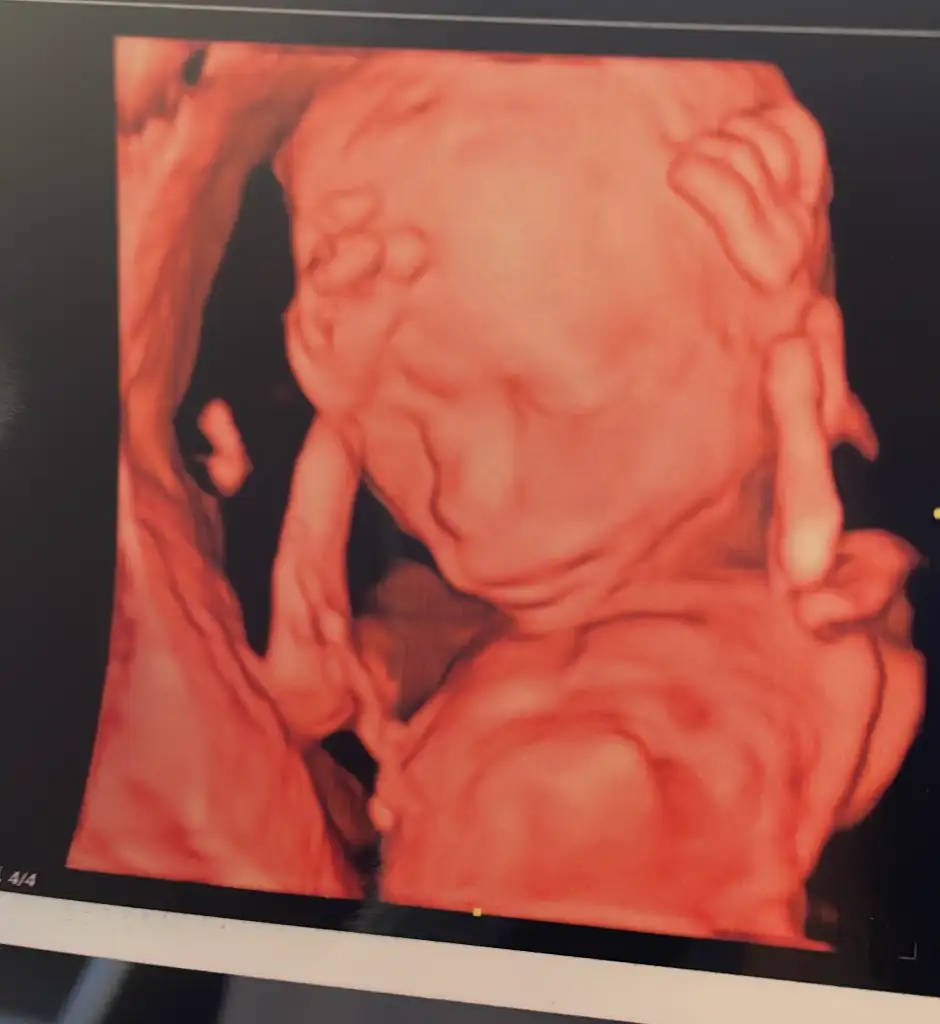

Maşallah canım.benim oğluşumun adını da yazar mısın? Ahmet Alp olacak nasipse inşallahKızlar bu da bizim kız ilk defa yüzünü gösterdi 18+2 doktor ağzı burnu küçük su içinde büyük duruyor dedine bana ne eşime benziyor benim babaanneme benziyor